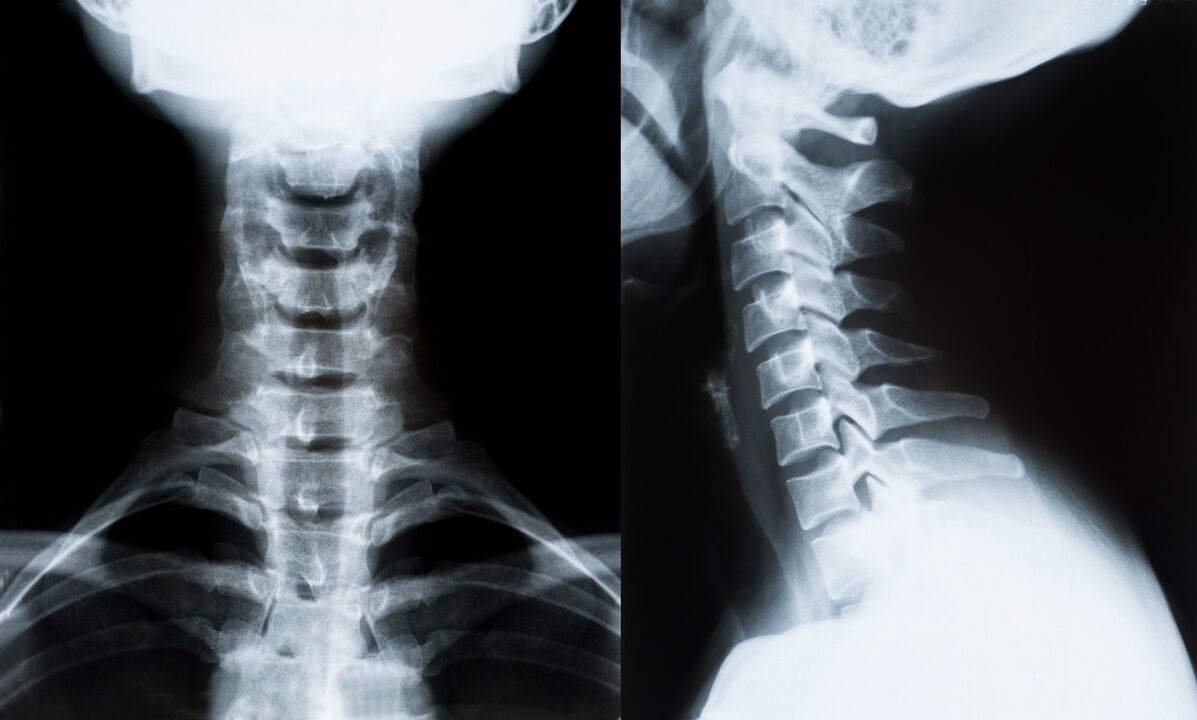

Los principales métodos de diagnóstico y determinación adicional del tratamiento de la osteocondrosis de la columna cervical:

- Radiografía. El método de diagnóstico menos eficaz, pero tradicional.

- La resonancia magnética es el método de diagnóstico más eficaz. Con este tipo de examen del paciente, todas las estructuras necesarias son visibles.

- Si es necesario medir cambios, se utiliza la tomografía computarizada. Determina la presencia de hernias y otras cosas.

- El último método es la ecografía dúplex. Este método de investigación determina la velocidad del flujo sanguíneo en las arterias.

Es imposible determinar con precisión la enfermedad de la columna en casa.